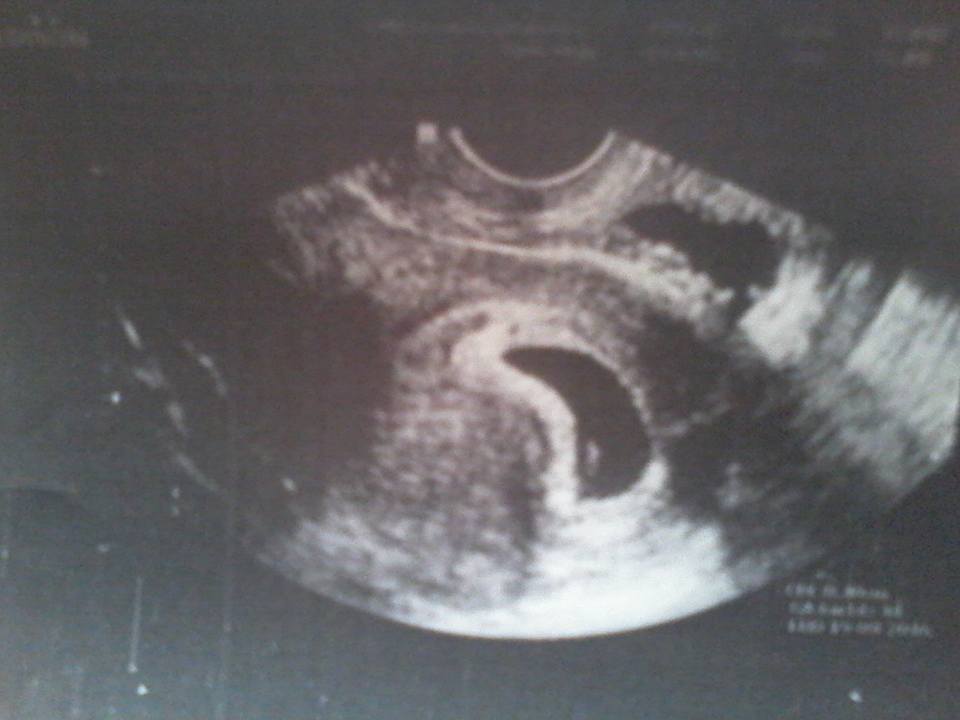

Ahoj holky co si o tehle fotce myslíte, já nevím všichni říkaj že tam vidí 2 váčky já jsme přesvědčená o tom že je tam jen jeden a to druhé nahoře sice nevím co je ale mimčo asi ne. Pokud by to druhé bylo snad by mi to doktorka řekla ne? :-O 😀 😅

@saries to nahoře bude pravděpodobně střevo :oD to dole je děloha a ta malá bílá tečka v ní, to je miminko 🙂

@saries kdyby byla dvě, tak jsou obě v jedný tý "dutině" - viděla by jsi tam dva malé bílé flíčky v jednom velkém černém fleku :oD

@anetka1701 to jen v případě jednovaječných dvojčat. Dvouvaječná by byla takto oddělená. Tady je to ale nejspíš střevo.

@anetka1701 Kdyby byly ve vacku 2 tecky, jsou to jednovajky, u dvojvajek ma kazdy svoji bublinku